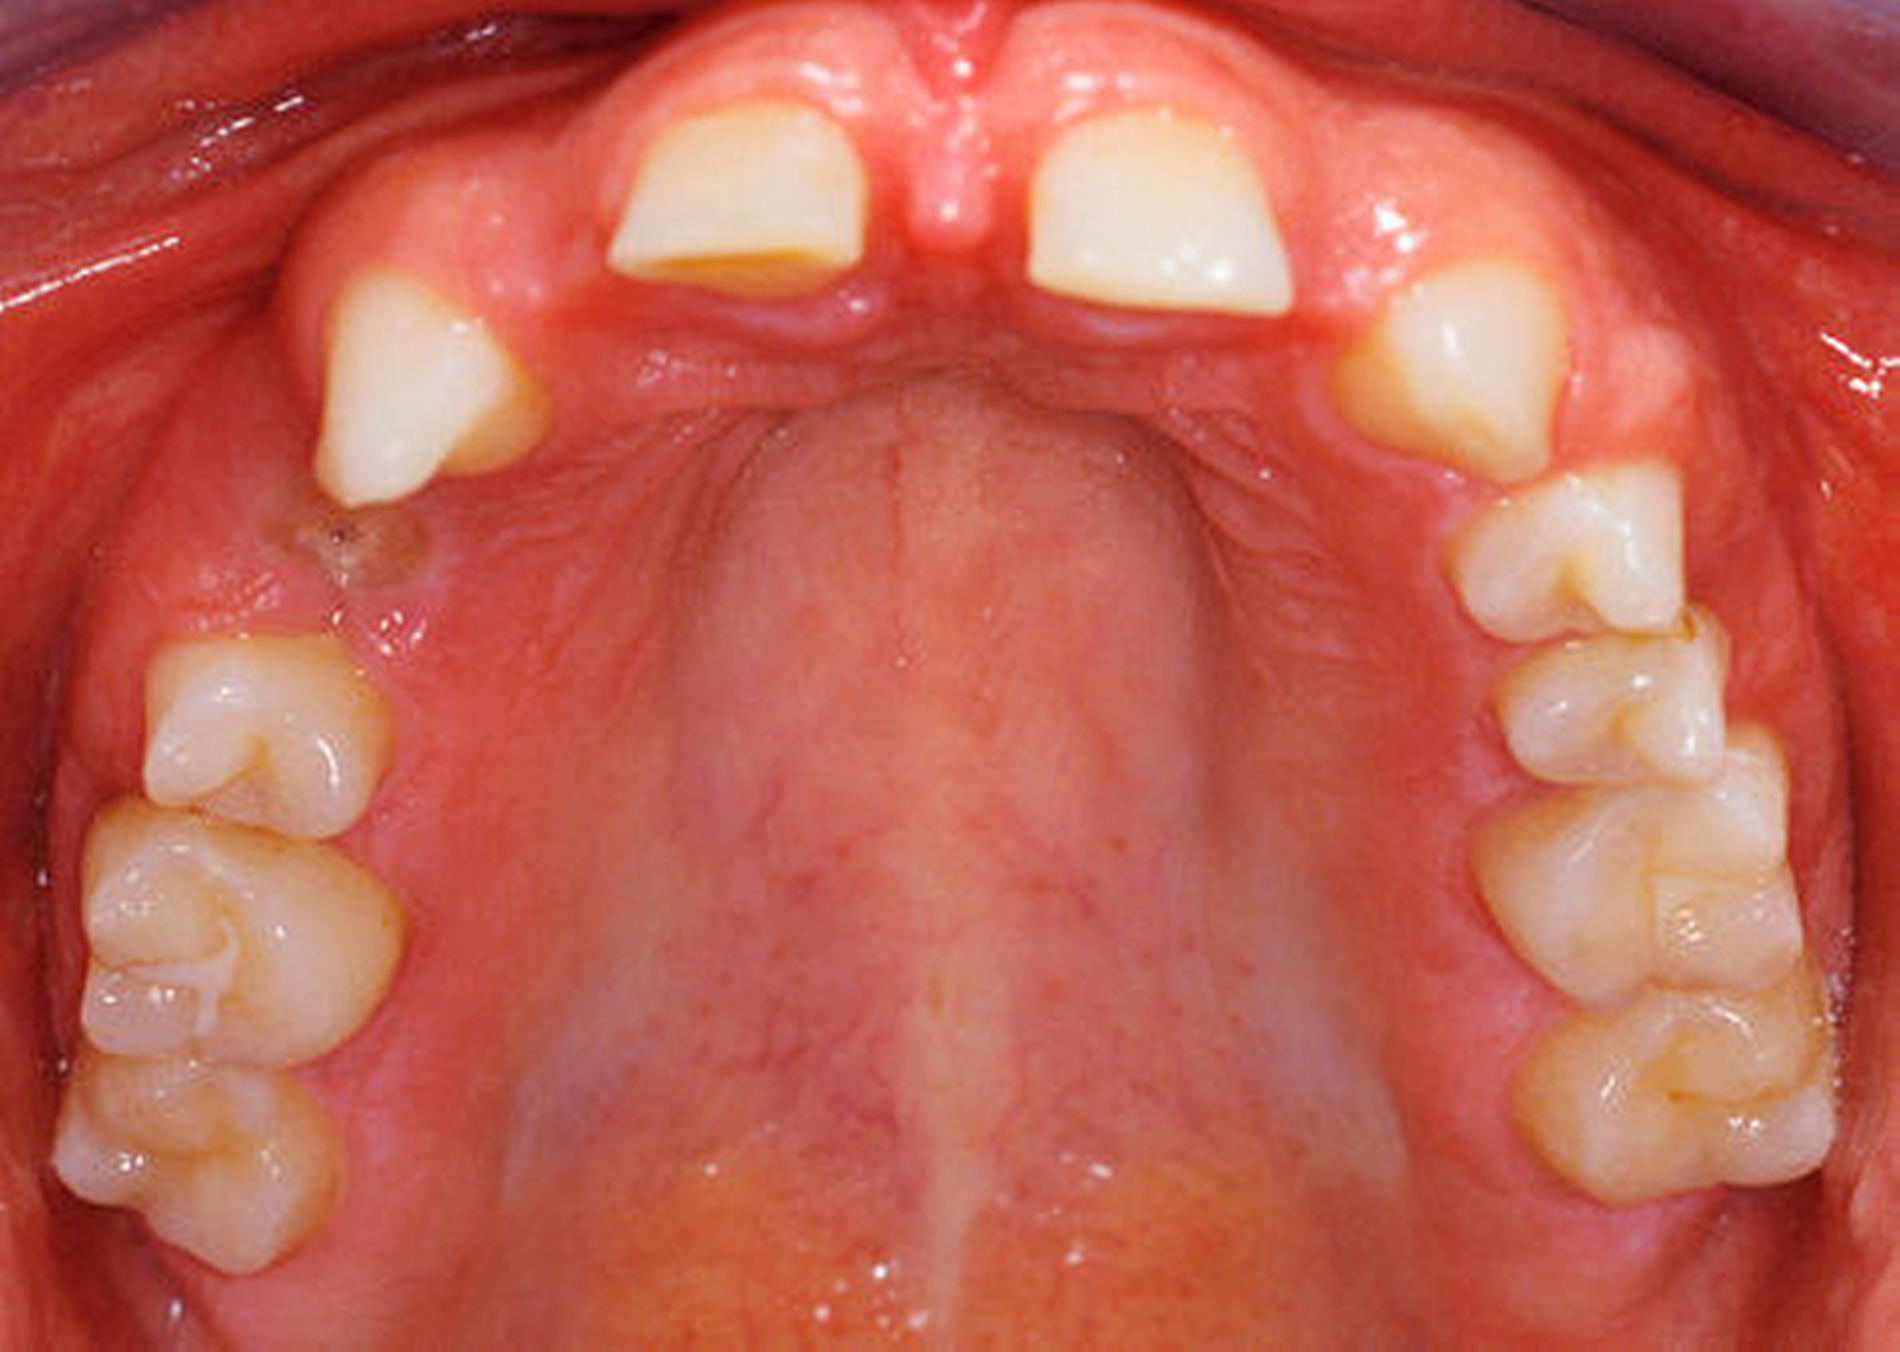

Die 16-jährige Patientin war unglücklich über ihre lückig stehenden Zähne und wünschte eine Verbesserung der durch die Dysgnathie beeinträchtigten Kaufunktion und ihres Aussehens (Porträtbilder en face und seitlich Abbildungen 1a und 1b, enorale Situation Abbildungen 2a bis 2c).

Anhand des klinischen Befunds, des Orthopantomogramms (Abbildung 3), der Durchzeichnung des seitlichen Fernröntgenbildes (Abbildung 4) und der Analyse der einartikulierten Modelle wurden folgende Diagnosen gestellt: skelettale und dentale Klasse II nach Angle (Distalbiss), Tiefbiss, Aplasie der Zähne 12, 14, 22, 34, 42, Persistenz und Infraposition der Zähne 54 und 74, Mikrodontie, starke Attrition der Oberkiefer- und der Unterkiefer-Front- und Eckzähne.